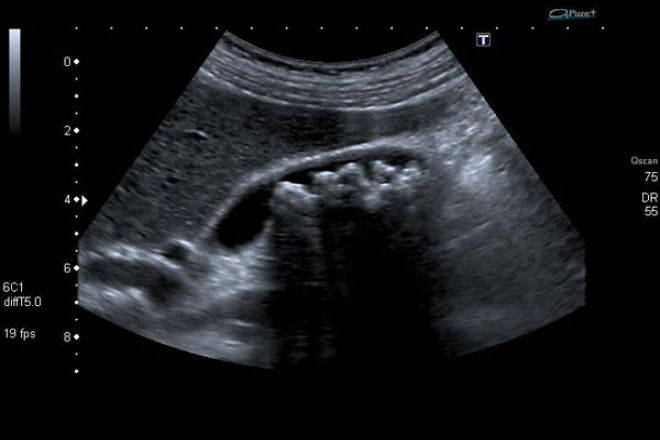

La ecografía abdominal, a menudo la primera opción diagnóstica, presenta una sensibilidad del 81% y una especificidad del 83% para la detección de colecistitis aguda. Sus hallazgos característicos incluyen engrosamiento de la pared de la vesícula biliar, presencia de líquido pericolecístico y un signo de Murphy ecográfico, donde se observa la interrupción de la inspiración durante la palpación por el dolor en el área del hipocondrio derecho.